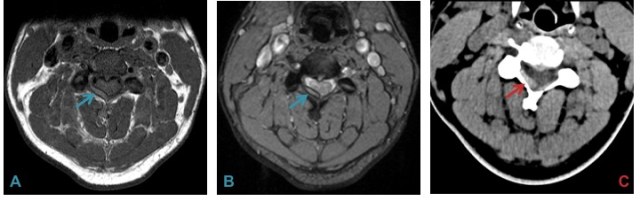

Relative T1 hyperintensity (A), hemosiderin rim (B) and hyperdensity on CT (C) aided in the diagnosis of epidural hemorrhage in this young patient. The cause of hemorrhage albeit, remained elusive after extensive work up.